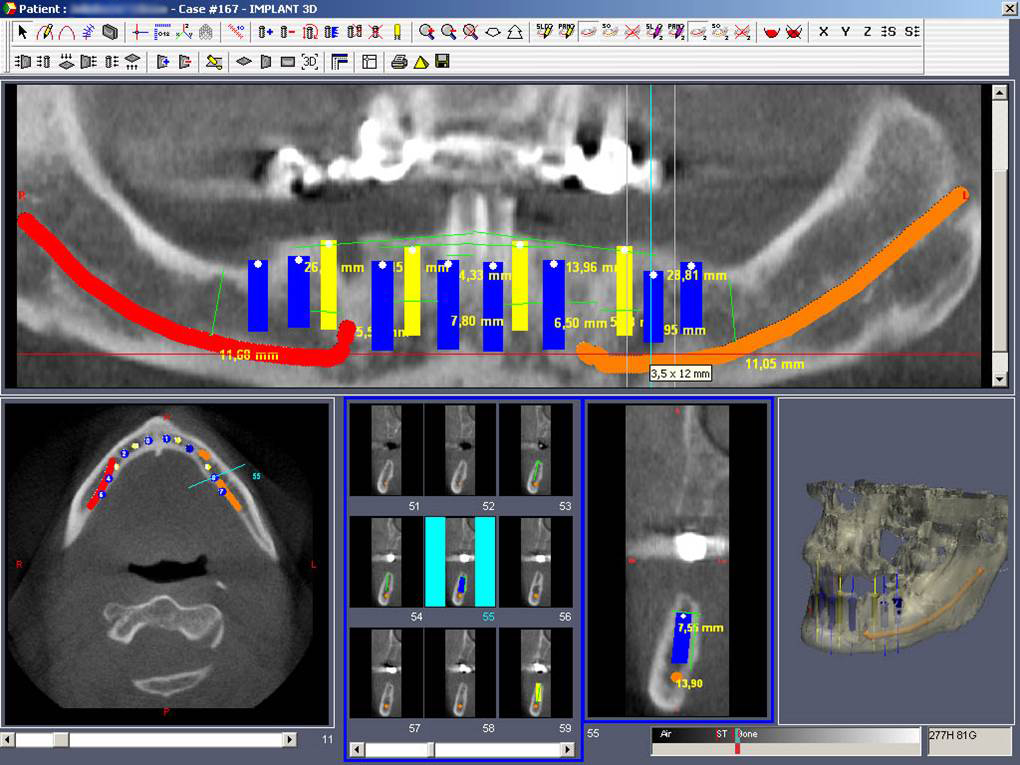

• Dokonalé vyšetření, stanovení diagnózy,naplánování ošetření - způsob, časový průběh,cena

Průměrná doba hojení implantátů před provedením definitivního protetického ošetření je 3-4 měsíce, v případech, kde je nutné doplnit chybějící kost (různé metody, postupy a materiály) – tzv. augmentace) se může doba hojení prodloužit na 8-12 měsíců. S tím je pacient vždy předem seznámen svým lékařem.